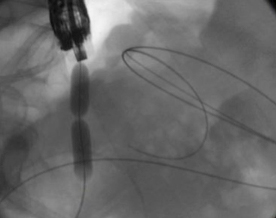

- Echoendoscopy: A stent is used to drain the pseudocyst by connecting it to an adjacent intestinal organ, using an endoscope with an ultrasound transducer at the tip.

The CADC team is evaluating a new pseudocyst drainage stent and delivery system which may be even safer and more efficient than other stents.